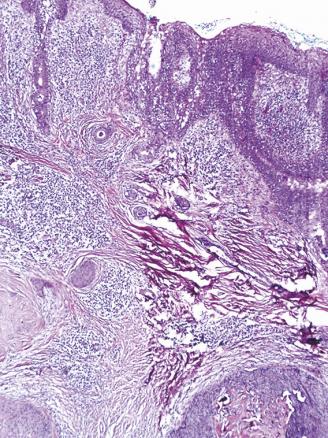

Cet homme de 40 ans, suivi pour un retard mental, consultait pour un placard papuleux blaschko-linéaire, s’étendant de la région médiocervicale à la région temporopariétale gauche évoluant depuis son bas âge, associé à de multiples nodules érythémateux suintants de la joue gauche et du cuir chevelu ainsi qu’à une lésion ulcéro-croûteuse frontale gauche (fig. 1 ). L’étude histologique montrait un hamartome sébacé et quatre tumeurs distinctes : un syringocystadénome, une tumeur combinée associant un syringocystadénome papillifère et un hidradénome, un trichoépithéliome et un carcinome basocellulaire nodulaire (fig. 2 et 3 ). L’examen ophtalmologique et l’IRM craniocérébrale étaient normaux. Le diagnostic d’un syndrome de Schimmelpenning-Feuerstein-Mims compliqué de tumeurs annexielles et d’un basocellulaire était retenu et le patient adressé en chirurgie maxillofaciale pour sa prise en charge.